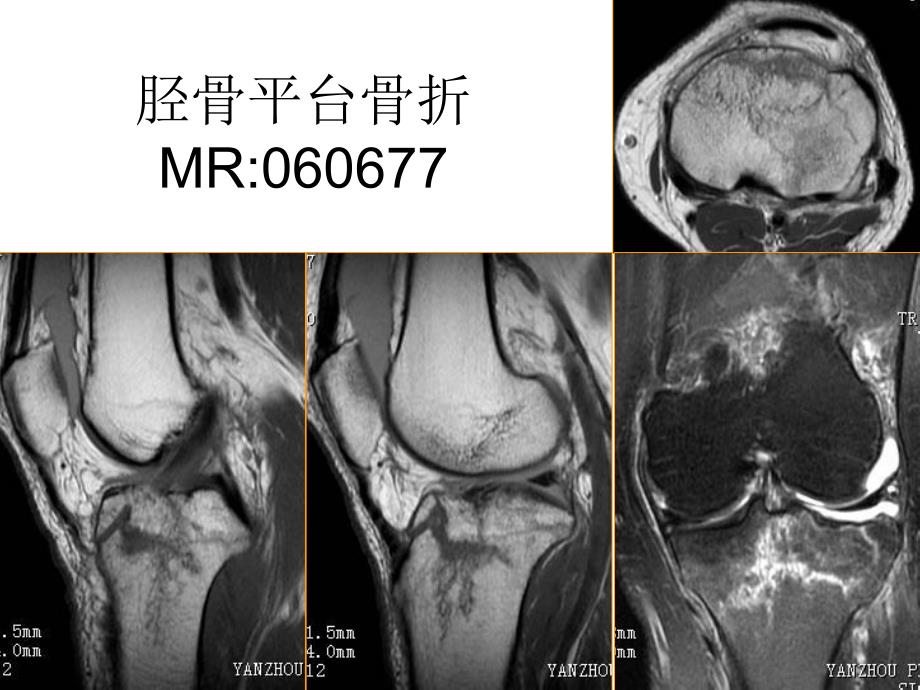

运动骨骼系统膝关节腔积液胫骨平台骨折MR:060677股骨内、外侧髁撕脱骨折胫腓骨粉碎性骨折左耻骨骨折左侧髂骨骨折左侧髋臼骨折 对侧正常跟腱跟腱损伤MR:060574骨肿瘤MR:061365骨软骨瘤CT:41161骨软骨瘤MR:061626肱骨恶性肿瘤MR072389肱骨恶性肿瘤MR072389脊柱、脊髓椎体压缩骨折,双边征C5棘突骨折并椎体前滑脱,C7椎体压缩骨折Sag T2WISag T1WISag fsT2WIC35水平颈髓损伤L1椎体压缩性骨折右侧横突骨折颈椎间盘髓核脱垂腰椎间盘髓核脱垂CE腰椎间盘突出椎管占位,脊膜瘤脊髓室管膜细胞瘤骶管蛛网膜囊肿椎管髓外硬膜内占位拴系综合症MR:060556